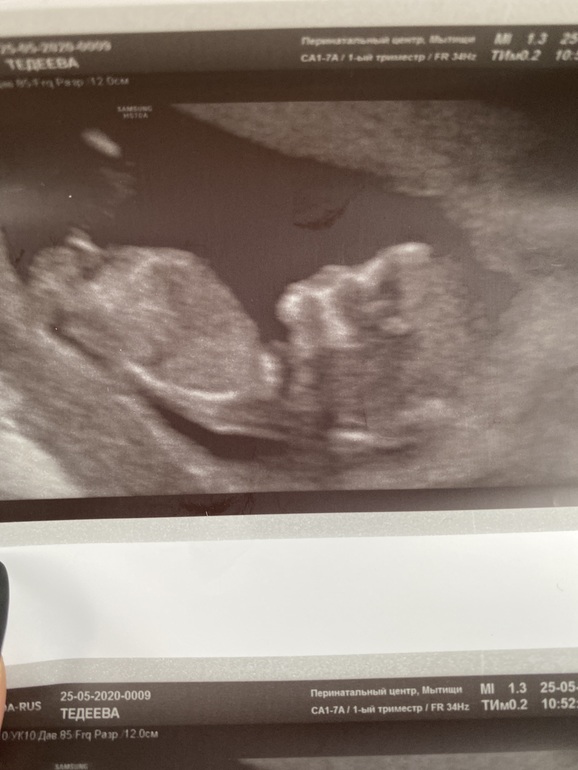

Пол малыша

Девочка))

Где это видно? Я не верю в такое счастье)

Ну вот на верхней фотке по половому бугорку)

мне тоже кажется, что девулечка!

По лицу предположу, девочка😜

Не 100% но мне похоже девочка

Пусть будет девочка)